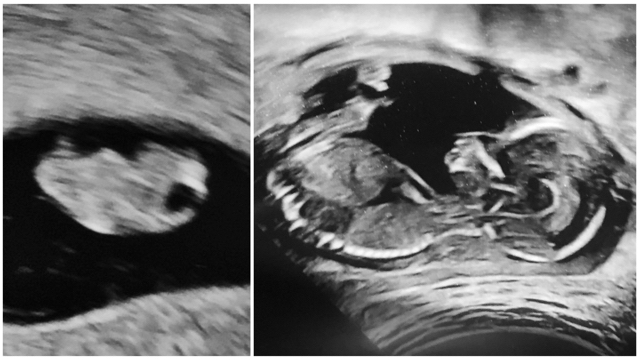

The difference 8 weeks makes

My baby boy at 8 weeks vs 16 weeks. He’s growing so fast!